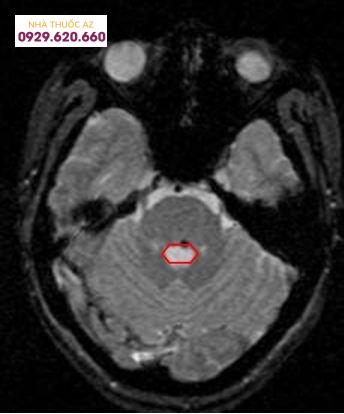

u-mau-hang-mot-di-dang-mach-nao-3

Chụp cộng hưởng từ sọ não chẩn đoán u máu thể hang

Để phát hiện u máu thể hang, khi khám, bác sĩ sẽ cho chỉ định chụp cộng hưởng từ sọ não, tùy từng bệnh nhân có thể tiêm thuốc hoặc không tiêm thuốc. Hiện tại, đây là phương pháp chẩn đoán u máu thể hang chính xác nhất bởi nếu chỉ định chụp mạch máu não sẽ không phát hiện được u máu thể hang.